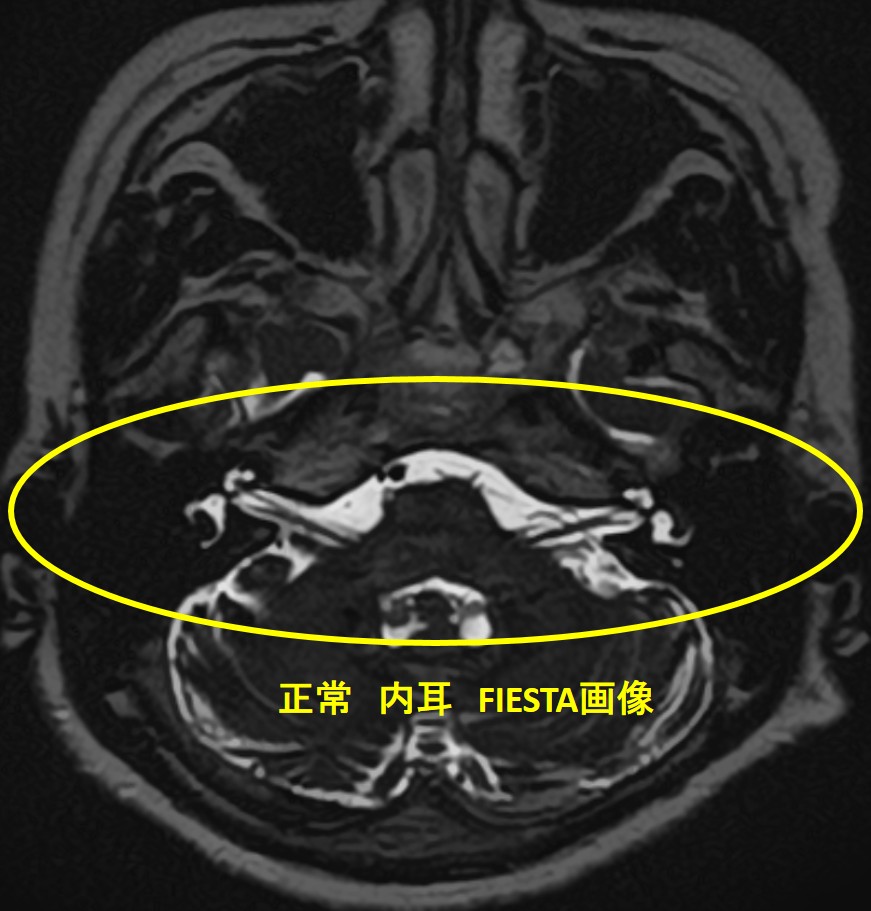

✅ 特殊撮影法(FIESTA/CISS)でさらに精度アップ

MRIの中でもFiesta(フィエスタ)やCISS(シス/キス)という撮影法を併用することで、聴神経・顔面神経・血管などの位置関係をミリ単位で識別可能。

これにより、早期診断・早期治療・聴力温存につながります。